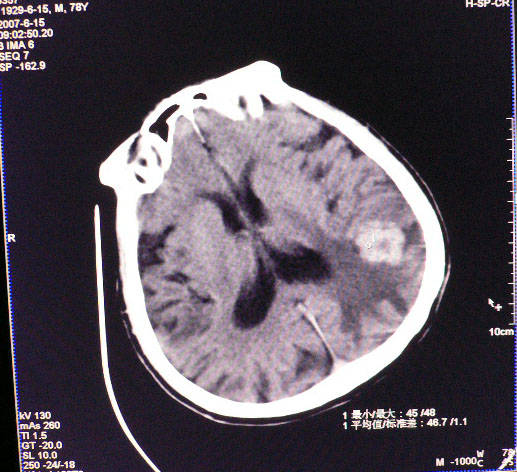

男性,78岁,失语,意识障碍1天

平扫ct值为40-45hu,增强为不均匀强化,ct值为81-85hu

皮层下厚壁花环状高密度影,明火显强化,大范围指样水肿,支持转移瘤诊断。其后上方好像还有小灶。

发生于质下,软组织影,形态不规则,周边大片水肿,明显环状强化,中间低密度液化坏死,建议结合临床